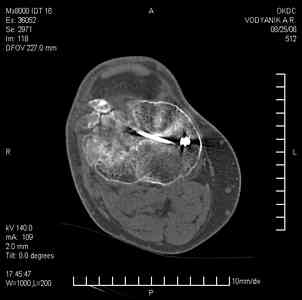

Уважаемые коллеги, В ортопедическое отделение обратился пациент: мужчина 47 лет, который в течение 4-х лет дважды получил травму костей, образующих правый коленный сустав.

В 2002 v внутрисуставной оскольчатый перелом проксимального метаэпифиза правой большеберцовой кости; в 2005 v внутрисуставной оскольчатый перелом дистального метаэпифиза правой бедренной кости.

В обоих случаях в разных лечебных учреждениях проводилось оперативное лечение переломов. При осмотре в отделении на основании результатов клинического осмотра и данных визуальных методов обследования поставлен диагноз: тугой ложный сустав дистальной трети правой бедренной кости, состояние после накостного остеосинтеза перелома типа 33-В2.2 ; несросшийся перелом надколенника; неправильно сросшийся перелом латерального мыщелка правой большеберцовой кости, состояние после металлоостеосинтеза перелома 41-В2.2; сочетанная осевая деформация правой ноги: варусная деформация правого бедра, вальгусная деформация правой голени; посттравматический артроз коленного сустава 4 ст по Kellgren-Lowrence; выраженное нарушение функции ходьбы и опоры.

Внешний вид ноги больного, данные рентгенографического обследования и избирательно выделенные компьютерные томограммы приведены в приложении. В именах КТ использовано кодирование уровня по АО, т.е. _41, например, означает проксимальную треть голени. В отделении намечен v очень предварительно v следующий план лечения: